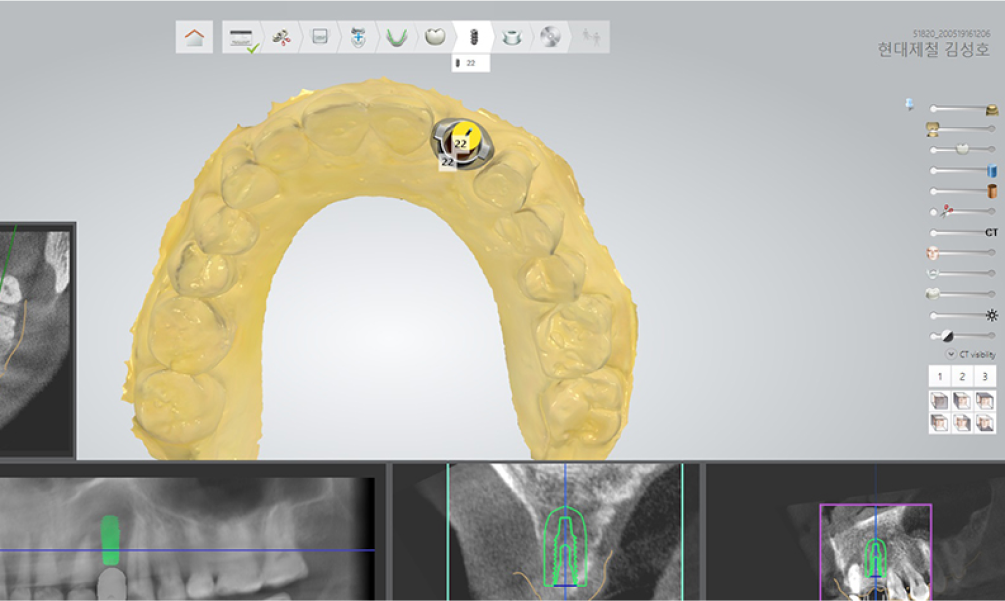

• 3D-CT

STEP 01 디지털 진단 & 컴퓨터 시뮬레이션

3D-CT를 이용해 치아를 정밀하게 분석하여 치아의 상태를 확인하며, 이 자료를 바탕으로 컴퓨터 시뮬레이션을 진행하여 임플란트 식립에 대한 모의수술을 통해 치료 계획을 세웁니다.